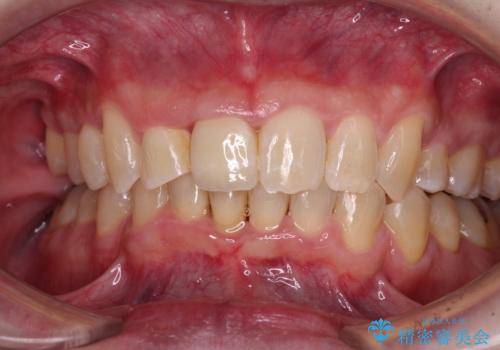

前歯が折れたついでに歯並びも改善 矯正治療と前歯のセラミック治療